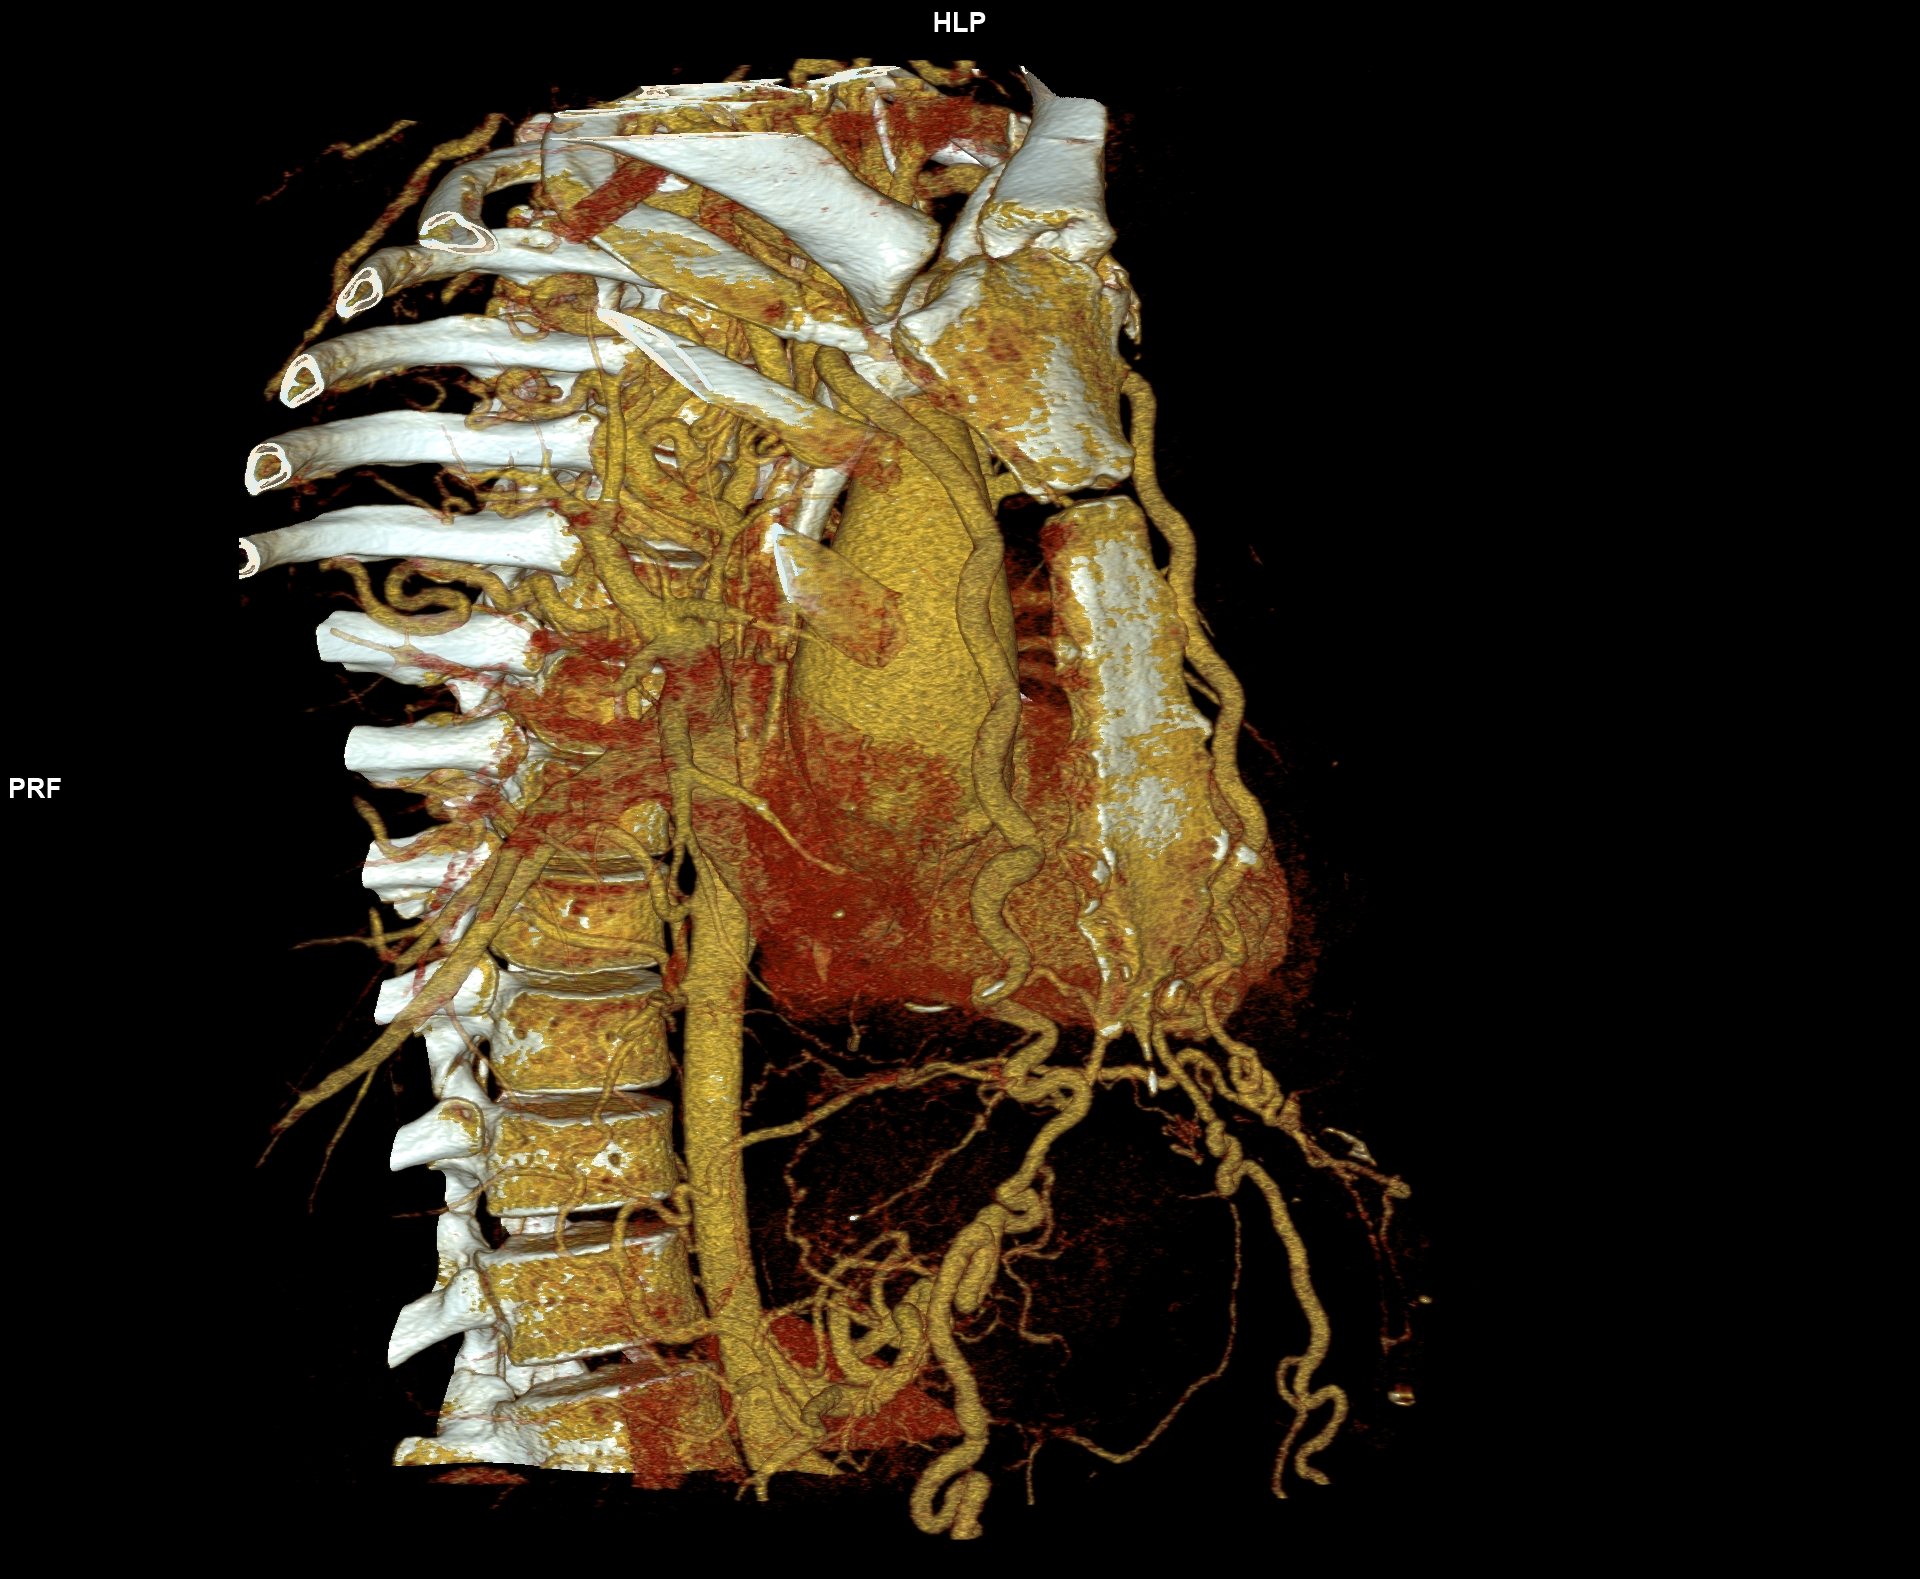

Figurile 6-10: reconstrucții volumice (VRT) din achiziție angioCT aorta toracică

Discuţie caz nr 109: Pacient cu suspiciune de coarctaţie de aortă – are indicație de angioCT aortă toracică; medicul radiolog la acești pacienți este indicat să efectueze investigația cu sincronizare ECG deoarece coarctaţia de aortă poate fi asociată și cu bicuspidie de valvă aortică, mai ales că la acest pacient ecografia cardiacă descria creștere de calibru a aortei ascendențe. Pe reconstrucția cine în planul valvei aortice din achiziția cardioCT cu sincronizare ECG se remarcă o valvă aortică morfologic tricuspidă, funcțional bicuspidă ce asociază ectazie de aortă ascendentă și coarctaţie de aortă descendentă cvasicompletă cu dezvoltare de circulație colaterală intercostală și mamară internă.